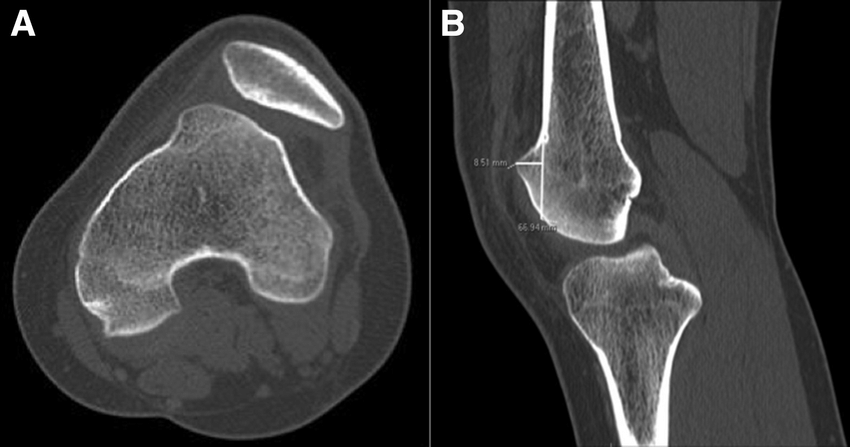

- وجود أجزاء معدنية قد يؤدي الى بعض التشويش و لا سيما فى أجهزة الأشعة المقطعية القديمة مثل ما فى الصورة التالية